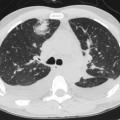

L’atteinte pulmonaire est variable : infiltrats alvéolaires, aspect en verre dépoli, nodules multiples excavés (fig. 9). L’hémorragie alvéolaire, complication majeure mais rare de la granulomatose avec polyangéite, se produit au niveau de la circulation pulmonaire distale entraînant un comblement alvéolaire (fig. 10). Elle se manifeste par une hémoptysie, une dyspnée, une anémie, des opacités diffuses alvéolaires et un liquide hémorragique au lavage bronchoalvéolaire (LBA). Des sténoses trachéo­bronchiques sont possibles.